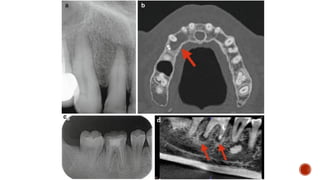

3- periapical pathology

Dr plays an integral role in assessing bone quality and quantity prior to

4- implantology